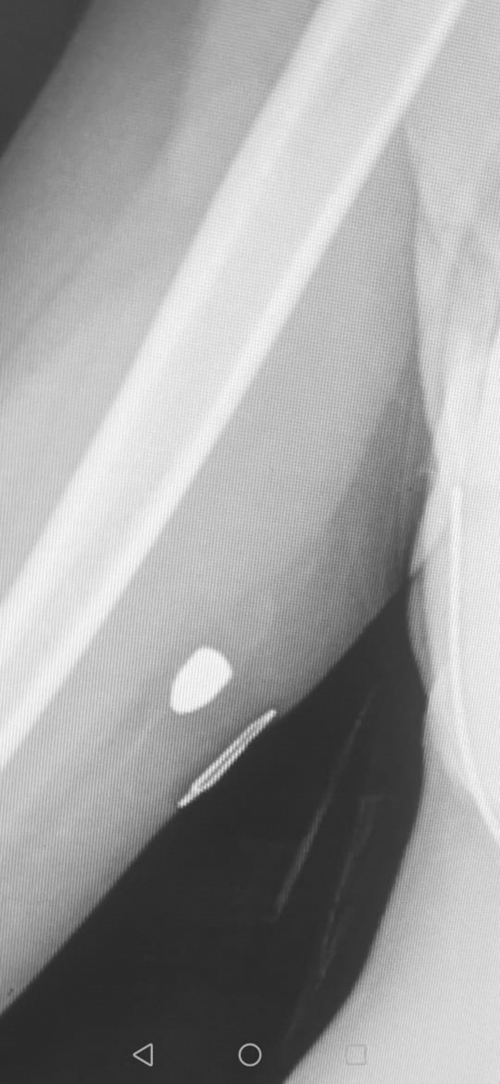

RICHARDS Bay High learner Coney Rossouw has unknowingly carried a bullet around, lodged in her upper arm, for the past nine months.

‘The first thought was that I had torn the triceps muscle, but after Dr van Niekerk ordered an X-ray it showed the bullet in my arm,’ said Coney.

‘We can only assume the bullet must have moved during the exertions. Besides the lump and the pain there is now evidence of inflammation.

‘Looking back at the incident on New Year’s Eve and the angle of the bullet’s trajectory down the arm, it appears a shot was fired up into the air from Alkantstrand,’ said Coney.